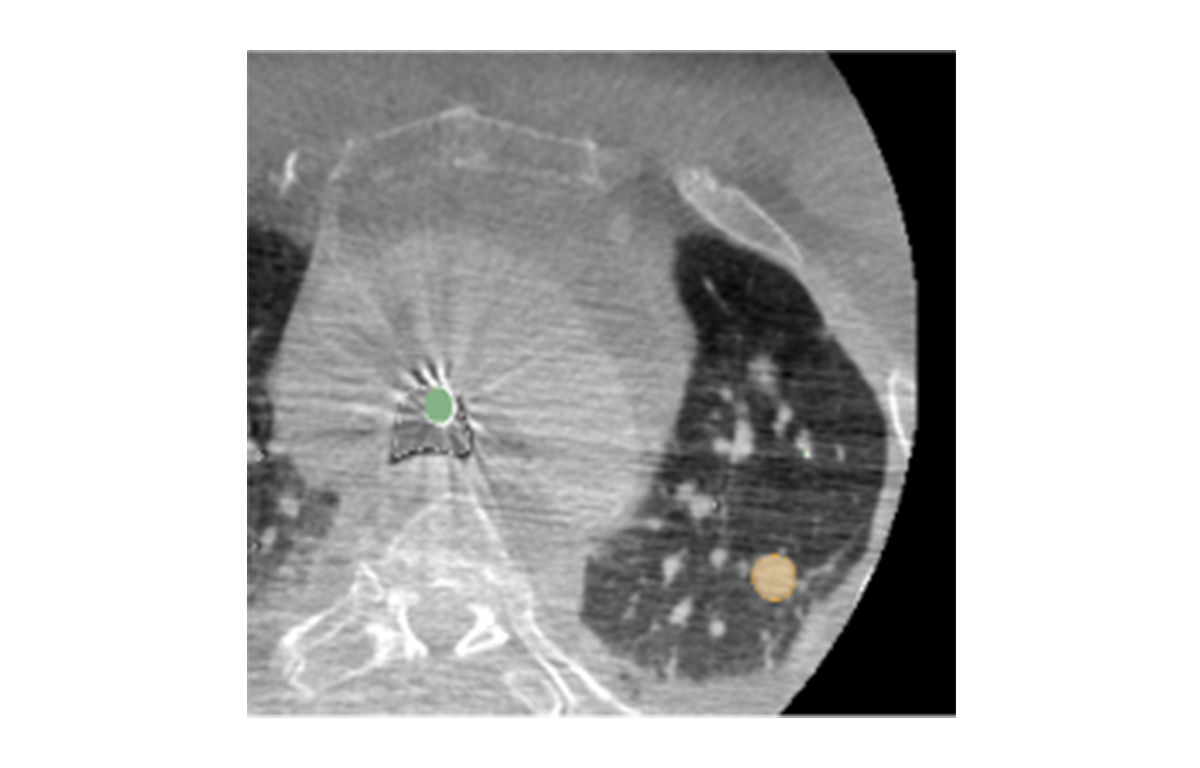

Built on advanced capabilities in lung segmentation and quantification, our AI technology interprets thoracic CT data with anatomical precision - capturing airway trees, parenchymal patterns, and vascular structures, even in severely diseased lungs.

Pre-operative planning of virtual bronchoscopy pathways

Lung Cancer

- Peripheral Lung Nodule Biopsy

- Tumor Ablation

- Local Drug Delivery

- Segmentectomy